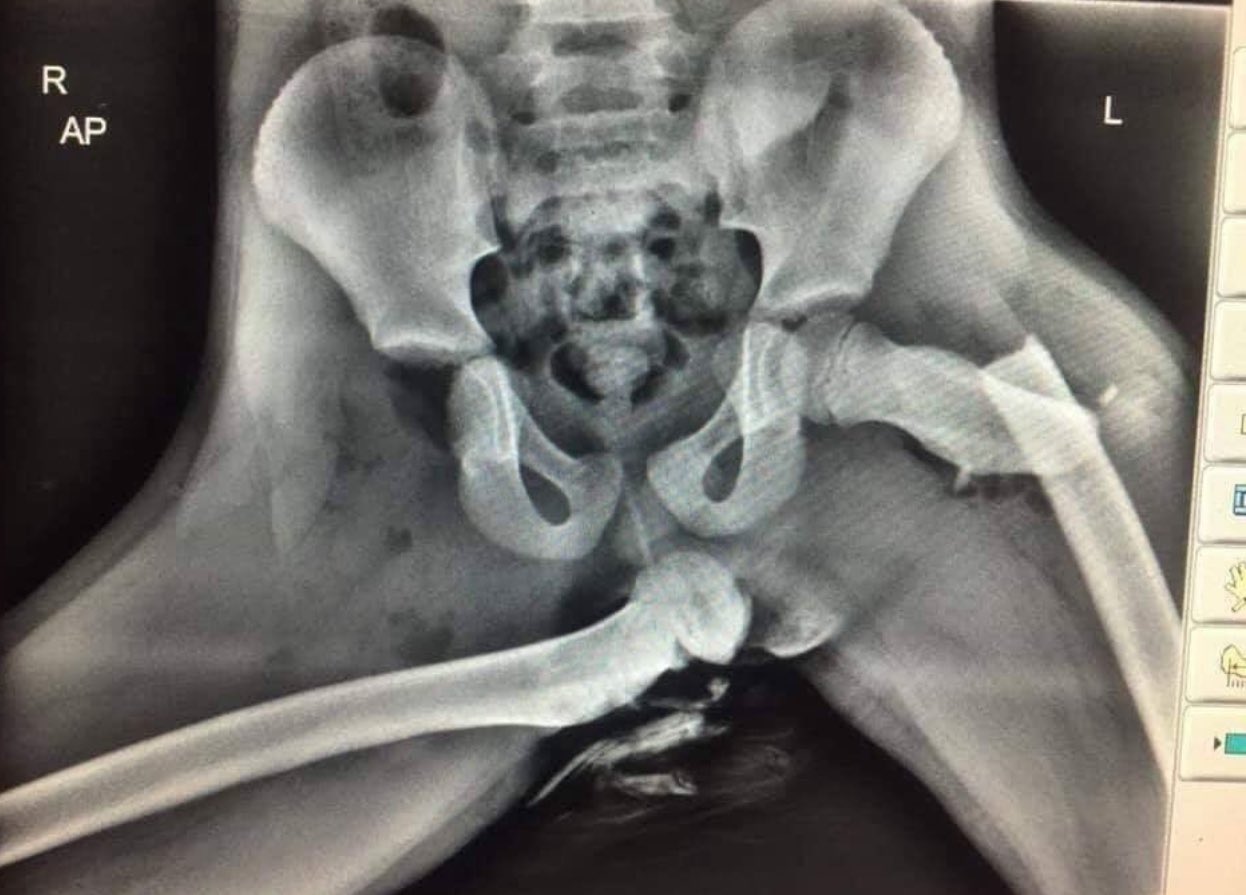

조수석에 다리 올리고 앉으면 안되는 이유...